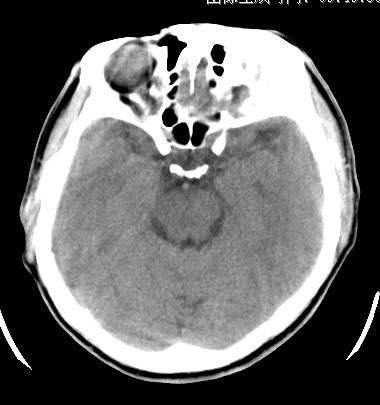

标题: CT17787:头ct,请帮忙看看右顶部有无异常 [打印本页]

标题: CT17787:头ct,请帮忙看看右顶部有无异常

男,58岁,偶有头疼

未见明显异常。右顶部低密度影为深入的脑沟。

增宽的脑沟!无异常!

是宽大的脑沟,局部不象有萎缩现象

增宽的脑沟

诊断依据:

低密度影周围脑组织边缘均有一层脑灰质覆盖。

正常啊,是对右顶增宽脑沟有疑问吗